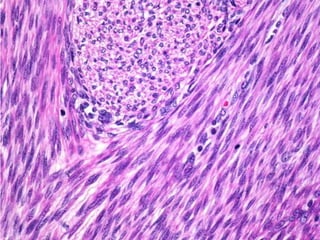

Carcinoma seroso do endométrio